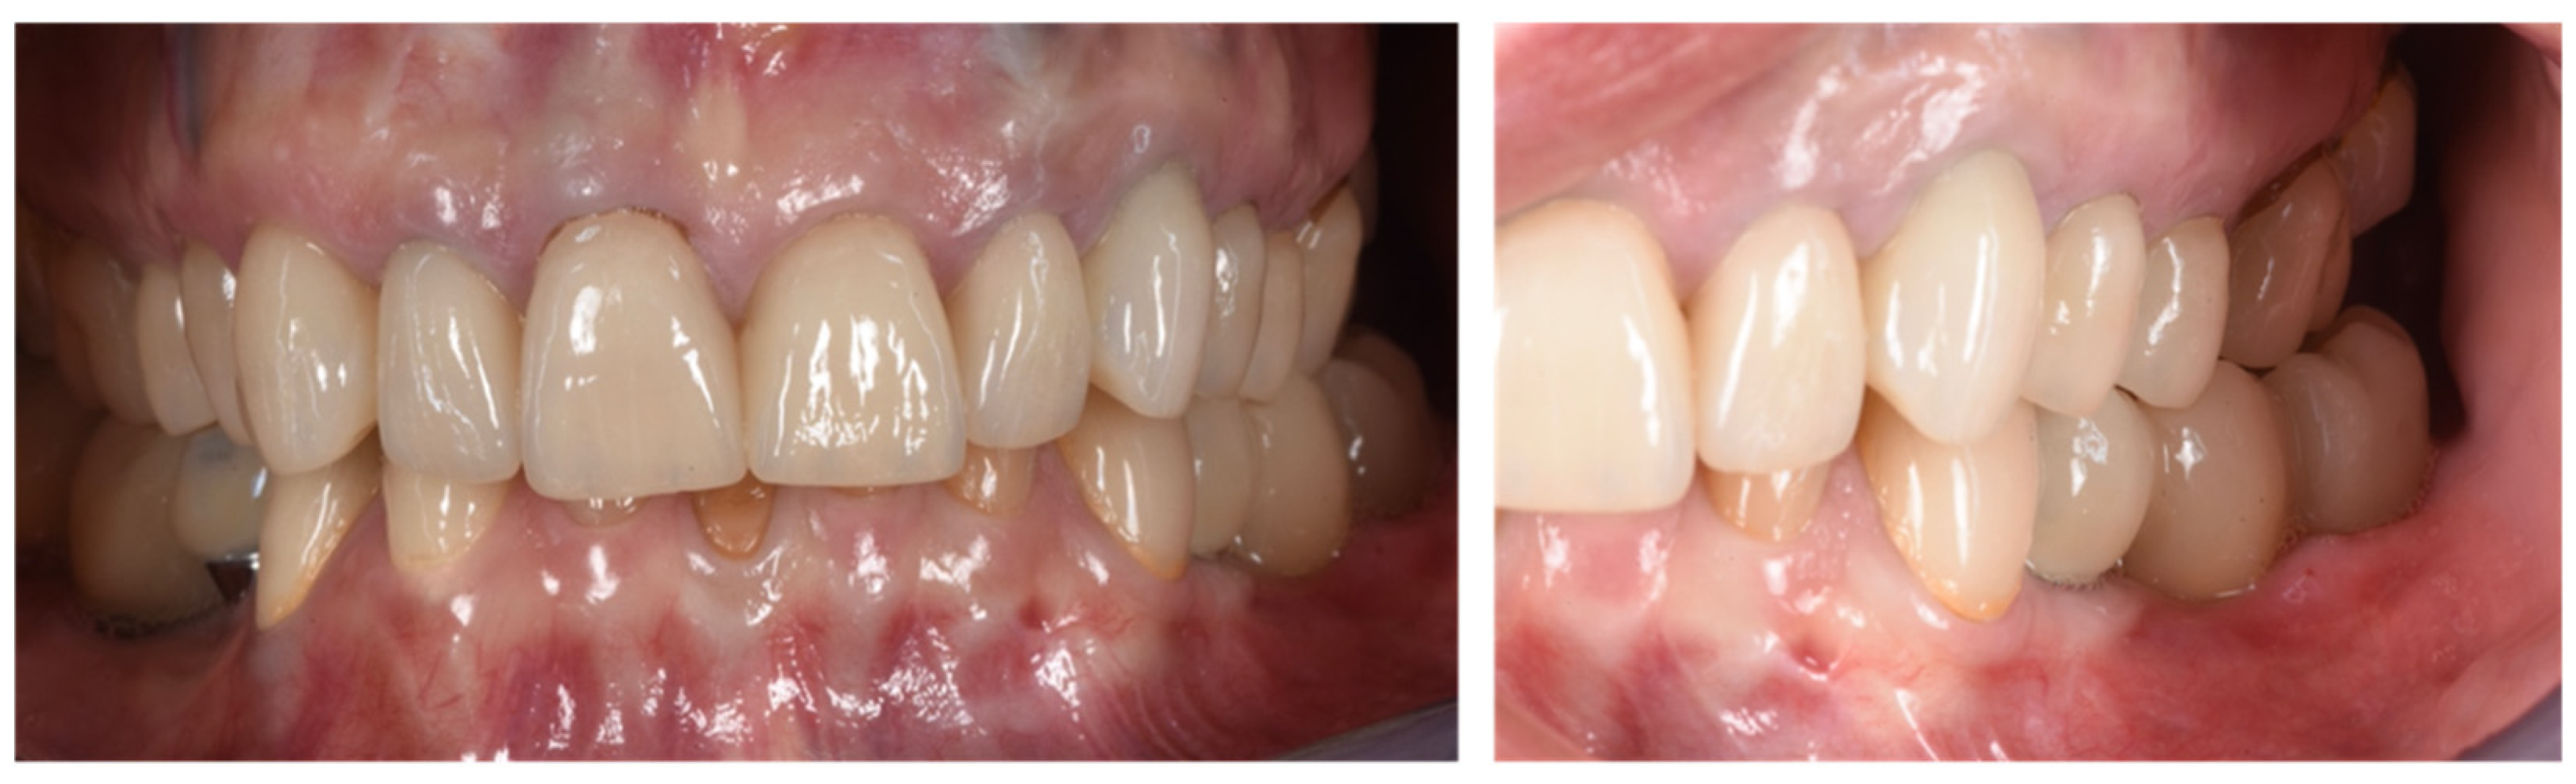

4. Conclusions

| T4 | Prosthetic Phase (14 months) | Delivery of the final restoration |

| T5 | Follow-up (26 and 32 months) | Clinical and radiographic evaluations |